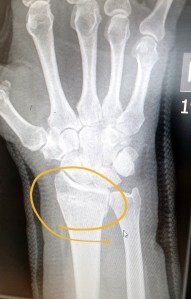

Unfortunately a particularly vicious shot at goal from a player, taking it all far too seriously, resulted in my dominant wrist being broken.

The cast was removed last week. I could feel something wasn’t right as I had lost the mobility in my thumb.

Today I had my first physiotherapy appointment. The break has healed well and I’ve already got a fair bit of movement back in my wrist and I can expect a full recovery.

Unfortunately the tendon in my thumb, the Extensor Pollicis Longus to be precise, has been severed at the site of the break and can only be fixed with surgery.